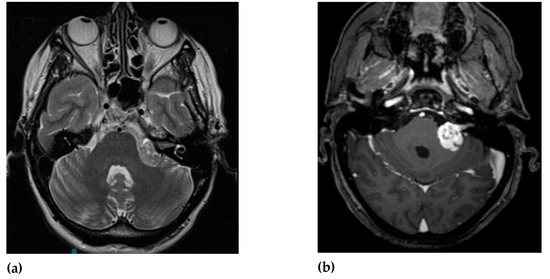

MRI is the standard imaging technique to assess the size, aspect, location and the evolution of VS. The ‘gold standard’ for diagnosing VS is the gadolinium-enhanced T1-weighted MRI sequence. Volume analysis using MRI imaging is preferred to evaluate the change in tumor size. A change of 20% in volume is considered clinically significant. Sometimes this can result in false-positive findings mainly with small lesion-like abnormalities [49,50]. T2-weighted MRI can help to show peritumoral oedema and the presence of cysts [51,52]. There are no major differences in MRI characteristics with routine imaging between NF2 VS and sporadic VS (Figure 1 and Figure 2).

VS are hypo- to isointense or isointense when compared to brain parenchyma on T1-weighted images [54,55,56]. Tumoral cysts are hypointense in comparison to the brain parenchyma on T1-weighted images [54,57]. The T1-weighted images can visualize intratumoral hemorrhage as an isointense or hyperintense area [58,59]. On T2-weighted images VS shows hyperintense signals [55,60]. The cysts of VS are hyperintense and the tumor can appear heterogeneous when there is cystic degeneration [58,61]. Hemorrhage can be seen as a hypointense signal on T2-weighted images [58]. Intratumoral hemorrhage can occur in VS due to its high vascularity [1,62]. Since T2-weighted imaging has high resolution and lower costs it can be used as the follow-up modality [63].